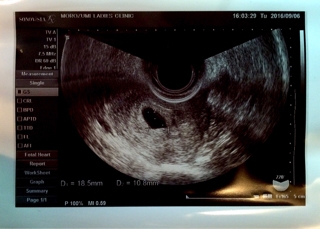

テーマ:不妊治療 BT32/D50(7w3d) ついに運命の日がやってきました…。 今日、心拍が確認できなければ、 その先は決まっています。 昨夜は緊張して寝付けず、 夜中にも起きてしまうほどでした…。 今日は1日有給休暇を取り、診察へ。 昨夜はプロジェクトの初飲み会だったため、なんとか参加しましたが、 やはり体調はあまり良くありません。 咽喉元ムカムカは変わらずだし、 めまいや頭痛もします。 ただ、座って何かを口に入れている事の方がまだ楽でした。 ◆9:50受付(10:...